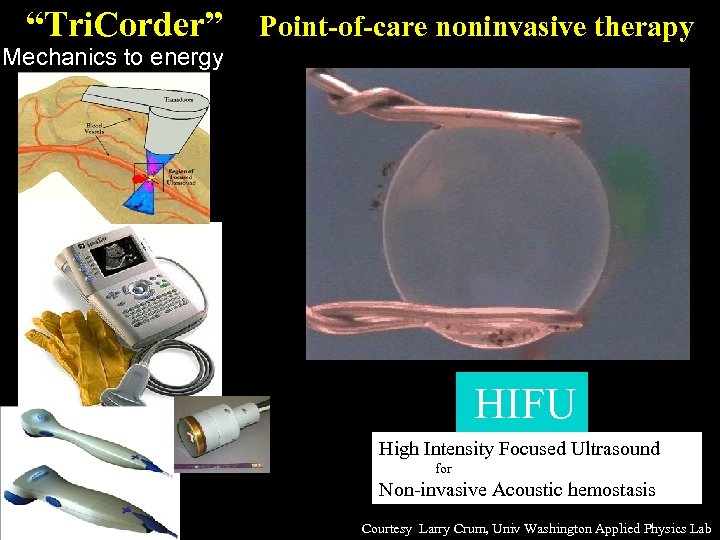

“Tri. Corder” Point-of-care noninvasive therapy Mechanics to energy HIFU High Intensity Focused Ultrasound for Non-invasive Acoustic hemostasis Courtesy Larry Crum, Univ Washington Applied Physics Lab

“Tri. Corder” Point-of-care noninvasive therapy Mechanics to energy HIFU High Intensity Focused Ultrasound for Non-invasive Acoustic hemostasis Courtesy Larry Crum, Univ Washington Applied Physics Lab